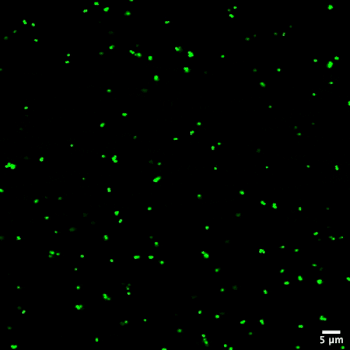

Bacteria can organize into biofilms, which can be helpful to humans in certain situations but harmful when they form inside the body. (More on biofilms in this previous post.) Biofilms are much more resistant to antibiotics than individual bacteria are, but scientists are still trying to understand why. Their slimy surfaces are hard to penetrate and the environments underneath are very different from the host—both of which may keep the antibiotic from working properly.